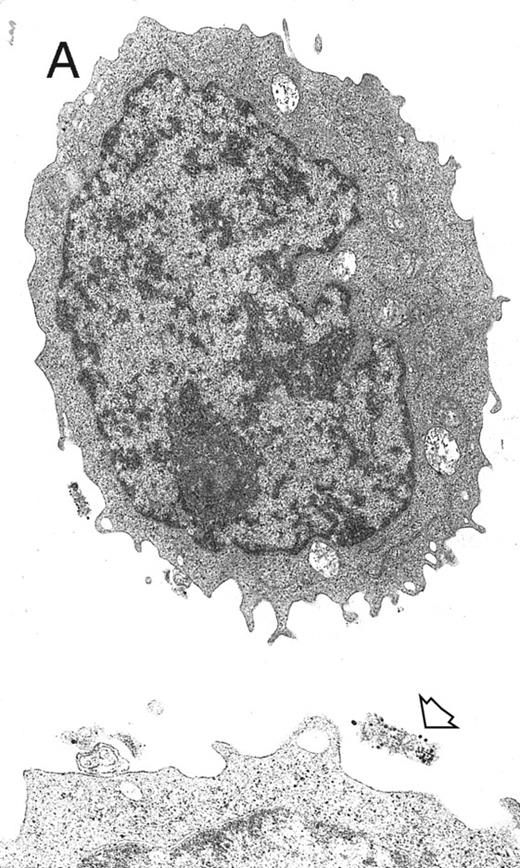

Electron microscopy.MP suspensions were fixed overnight with 2% glutaraldehyde in PBS at 4°C. A rinse in PBS of the specimen preceded the 1 hour of postfixation in 1% OsO4 in PBS at 4°C and wash in distilled water. On the same occasions, fixed MP were incubated with anti-CD61 antibodies (clone VPL2; kindly provided by W. Knapp, Wien, Austria) and with goat antimouse IgG conjugated with 15-nm colloidal gold particles (Jansen, Beerse, Belgium). Dehydration was performed using a graded ethanol series from 70% up to 100% and propylene oxide. After embedding in Araldite, ultrathin sections (silver or very pale gold) were obtained with a Reichert Jung ultramicrotome, counterstained with uranyl acetate and lead citrate, and observed with a CM10 transmission electron microscopy at 80 kV (Philips, Eindhoven, The Netherlands).

Electron microscopy evaluation of MP generated from purified CD34+ cells cultured for 7 days in the presence of MIP-1α, IL-3, IL-6, IL-11, FL, SCF, and MGDF. In (A) (original magnification × 11,230), an MP cell shows a sparse chromatin, a nucleolus, and few vacuoles and polyribosomes; the cell outline shows some microvilli and few gold particles indicating CD61 labeling (see arrow in the inset; original magnification × 25,120). A significantly more pronounced CD61 labeling is shown in the more differentiated MP in (B) (original magnification × 9,250).